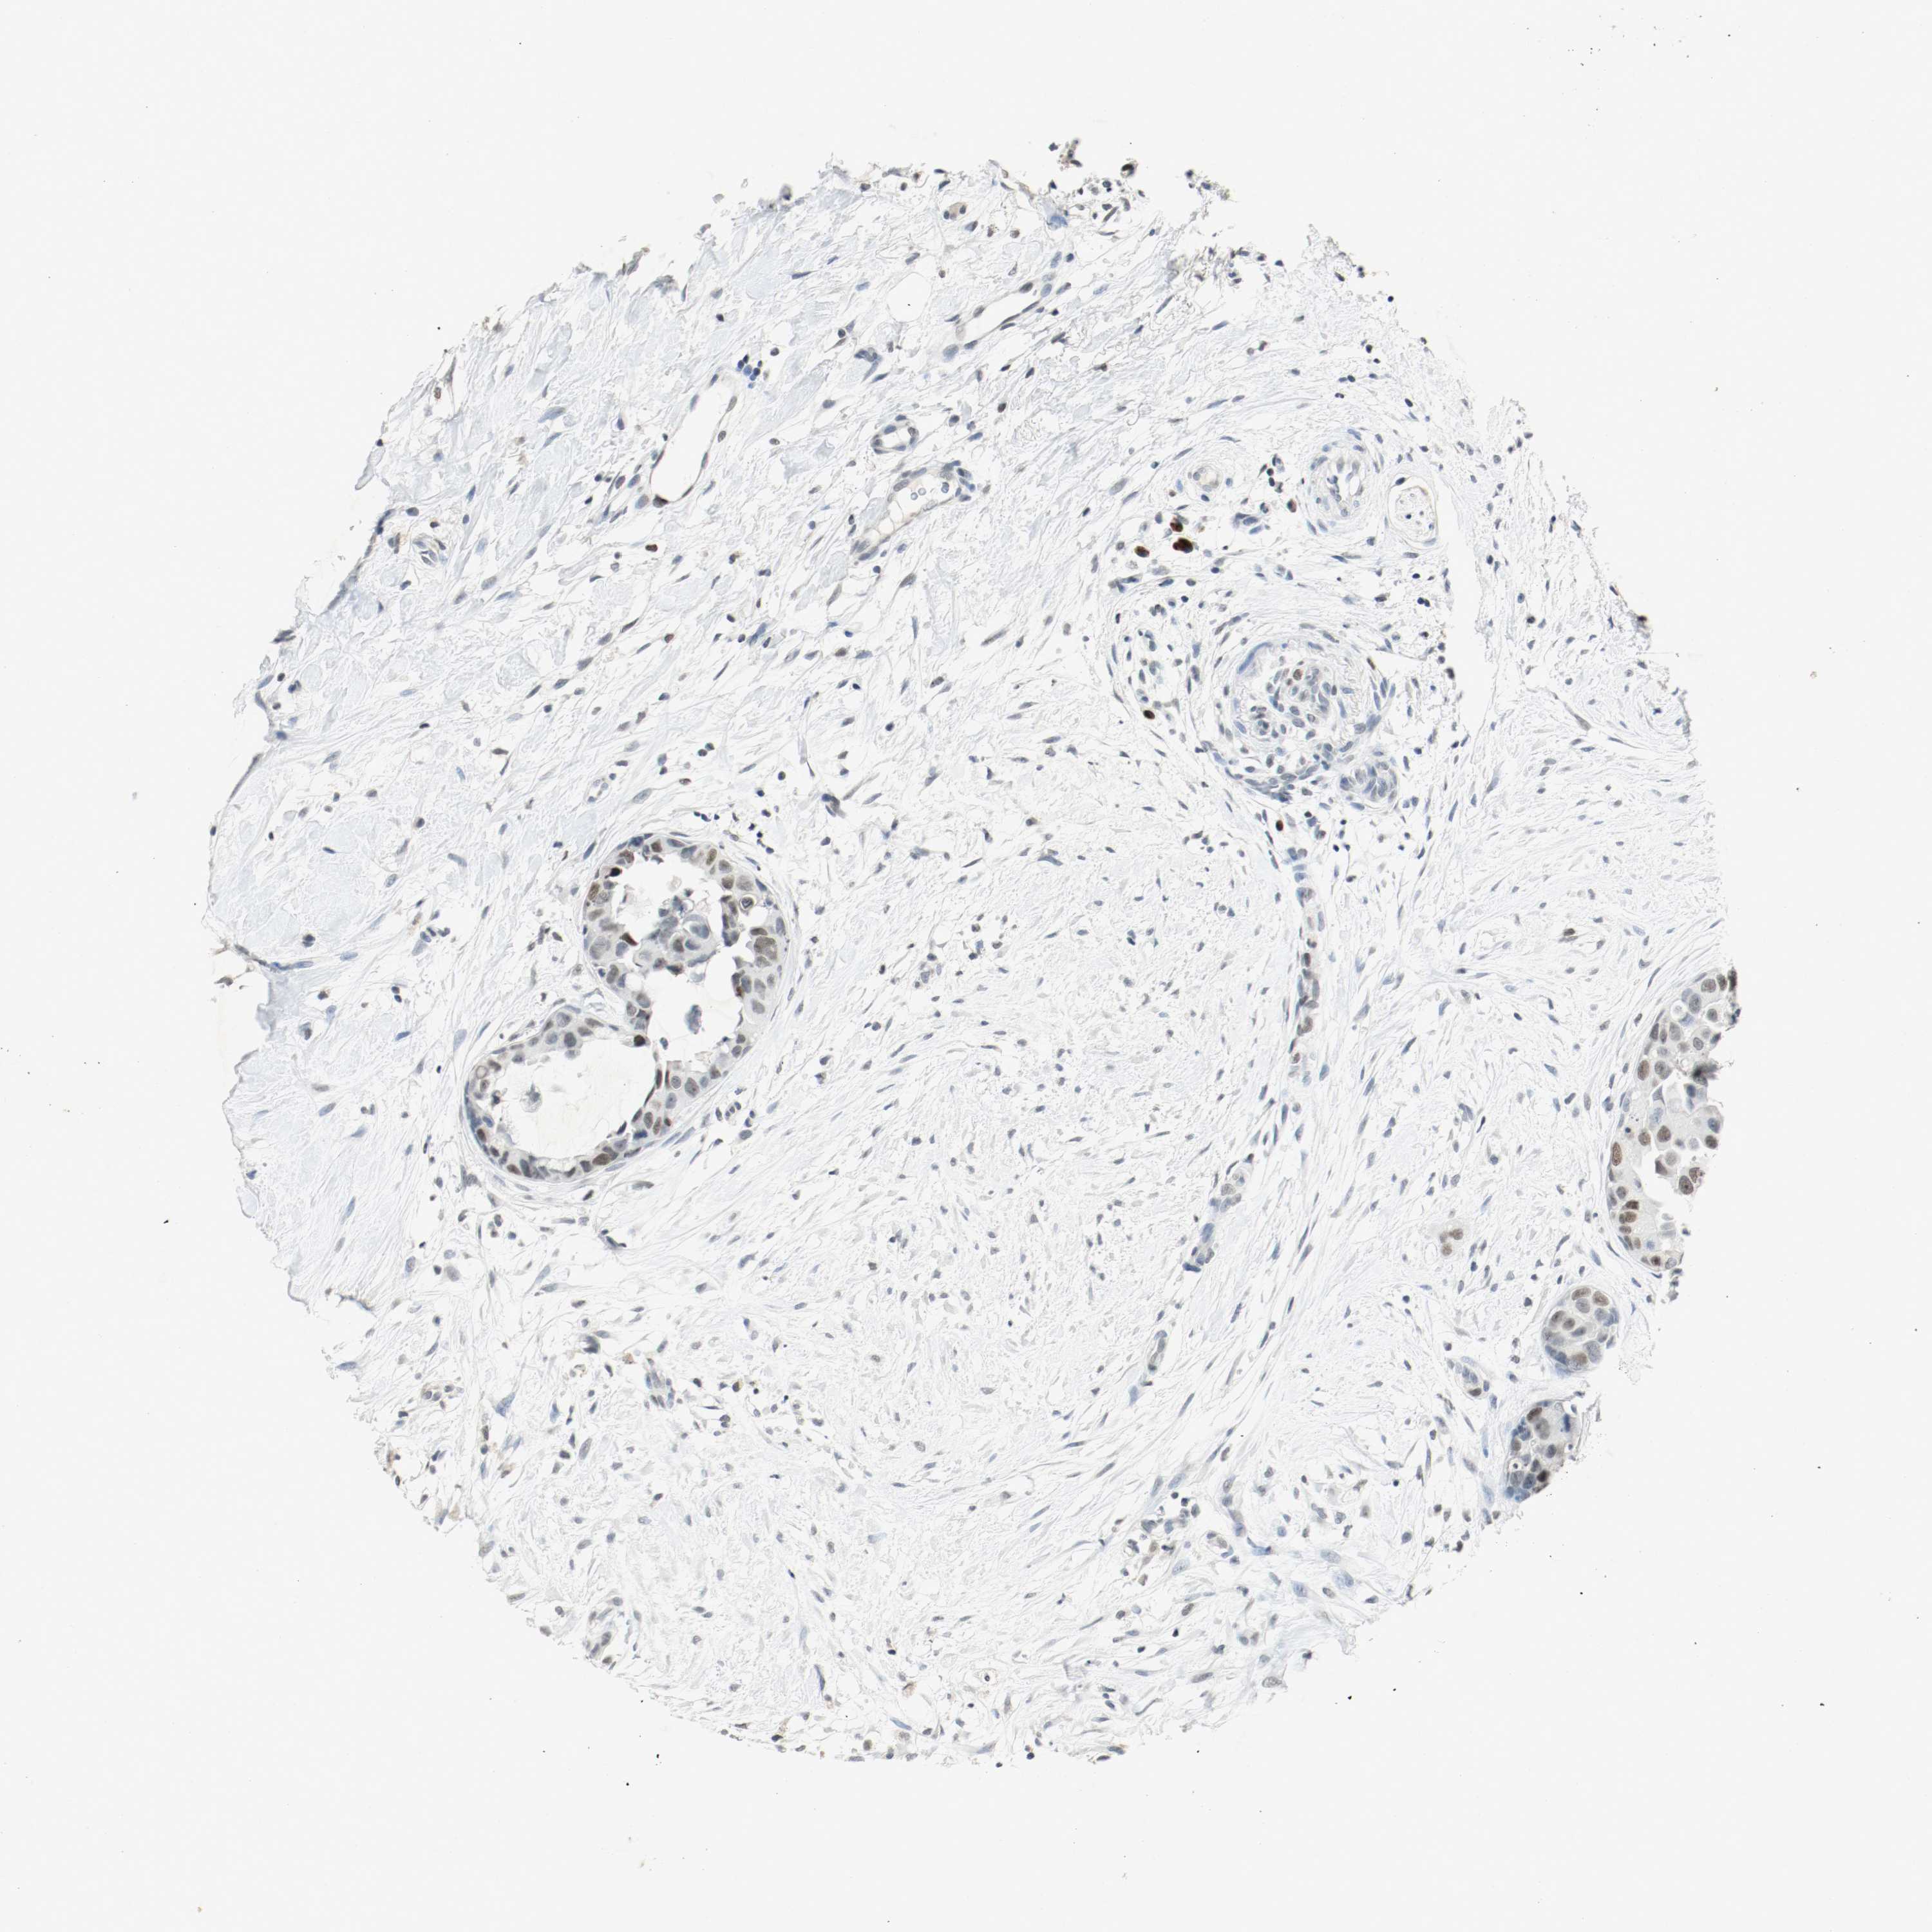

BRCA TCGA BRCA VALIDATION PROTEIN EXPRESSION

Breast cancer

Human cancer